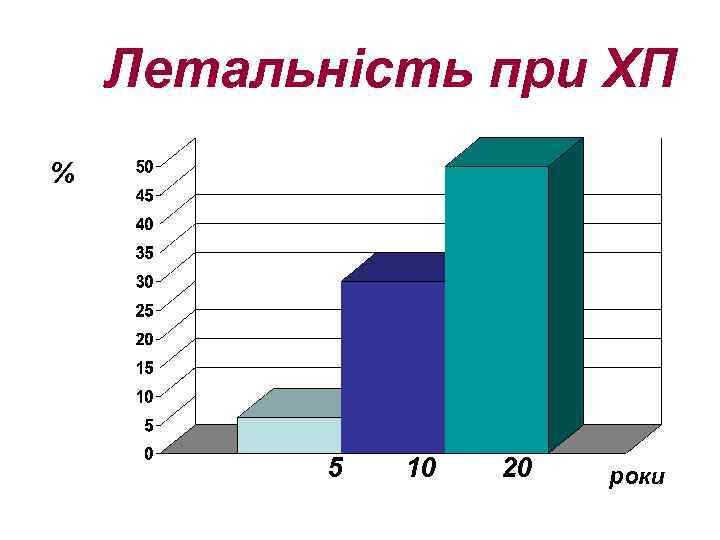

Летальність при ХП % 5 10 20 роки

Летальність при ХП % 5 10 20 роки